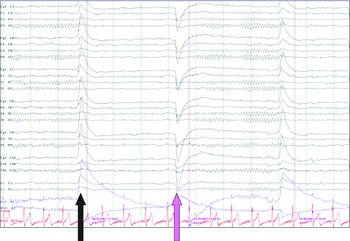

In some cases, it is not possible to determine the normality or abnormality unless a previous EEG is available for comparison. The normal low-voltage background pattern also tends to show well-defined and prominent photic driving responses with high-frequency photic stimulation. The measurable alpha rhythm may also appear during hyperventilation. In some normal people, the background activity is low voltage initially but may show measurable alpha rhythm in the latter portion of the recording. It doesnt show if theres any damage or physical abnormalities in your brain. 6 In some cases, it is difficult to differentiate if the low-voltage activity is abnormally Abnormal EEG Patterns correlation with underlying cerebral lesions and neurological diseases Suthida Yenjun Definition of the abnormal EEG An EEG is abnormal if it contains Epileptiform activity Slow waves Amplitude abnormalities or Deviations from normal patterns In most abnormal EEGs, the abnormal patterns appear only. An EEG test only gives information about the electrical activity in your brain. 5 There is some evidence that genetic factors play a role in determining the voltage pattern in a healthy person. The two main types of slowing are focal and generalized slowing. EEG can provide evidence for underlying diffuse or focal cerebral dysfunction through demonstration of background slowing.

Approximately 10% of normal subjects show a low-voltage (<20 µV) background pattern that is difficult to measure. The Abnormal EEG - Electroencephalography (EEG): An Introductory Text and Atlas of Normal and Abnormal Findings in Adults, Children, and Infants - NCBI Bookshelf.